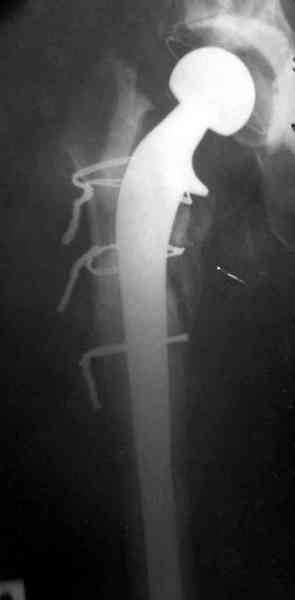

Наглухо ушитая рана с дренажом зажила первично, после чего с больной потерял контакт, и только недавно, через 8 лет я осмотрел её. Она без проблем нагружает на конечность и передвигается с помощью трости. От окончательной операции по реконструкции отказывается, довольная результатом.

Имеются литературные данные, когда спейсер держали не более 6 месяцев, но этот случай бьет все рекорды, может быть для наших людей, обременных финансовыми трудностями, нужна другая шкала оценки сроков нахождения спейсеров.

№3-6 снимки с осложнением

и последние снимки.